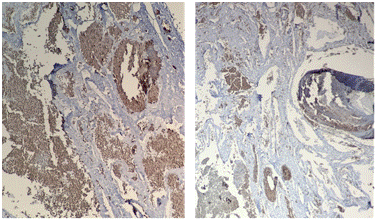

También se realizaron técnicas complementarias, de histoquímica (Tricrómico de Masson) (Figura 4) y de inmunohistoquímica para el anticuerpo GLUT1 (Figura 5), confirmando así el diagnóstico de un tumor de origen vascular.

Figura 5: La positividad para el anticuerpo GLUT 1, permitió tipificar a esta lesión vascular como un hemangioma. Técnica de Inmunohistoquímica para el anticuerpo GLUT 1.